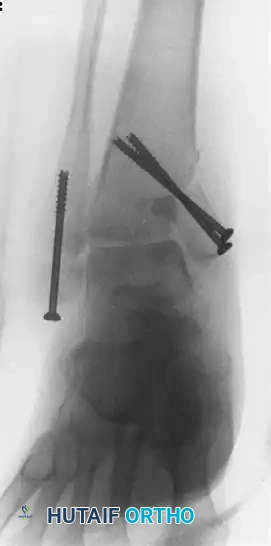

دراسة حالة مراجعة جراحية لكسر كاحل مزدوج

الصور الإشعاعية التالية توضح حالة معقدة لمراجعة جراحية لكسر كاحل مزدوج التأم بشكل خاطئ. في البداية، تم تثبيت الكسر بمسامير، ولكن التثبيت فشل وتطور إلى اندمال معيب مصحوب بانزياح في عظمة الكاحل.

لإنقاذ المفصل واستعادة وظيفته، تم إجراء تدخل جراحي معقد. تم قص عظمة الشظية، إطالتها، وتثبيتها باستخدام شريحة معدنية. كما تطلب الكعب الداخلي ترقيعاً عظمياً لملء الفراغ الناتج عن القص التصحيحي.